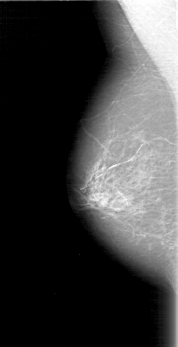

D_4097_1.RIGHT_MLO

RIGHT_MLO LINES 5191 PIXELS_PER_LINE 2656 BITS_PER_PIXEL 12 RESOLUTION 43.5 NON_OVERLAY